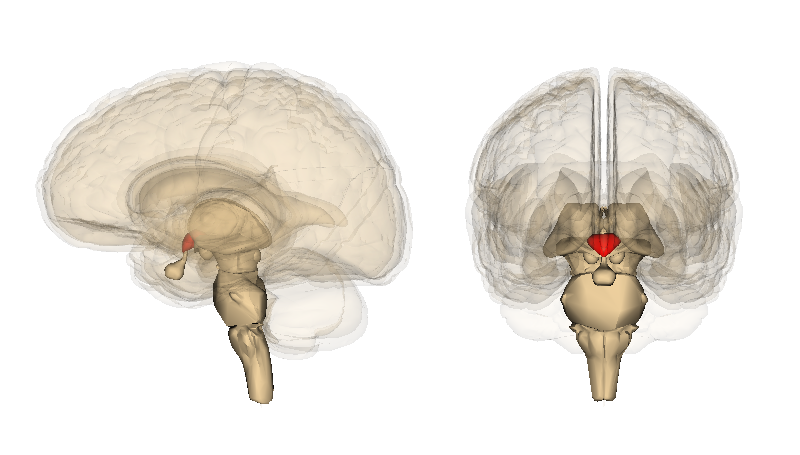

視床下部 Life Science Databasesより

エネルギーの必要性に応じて摂食行動を調整する恒常性系は、視床下部に存在する摂食促進系摂食抑制系という拮抗する2つの経路から構成されています。

前者にはニューロペプチドY(NPY)やアグーチ関連タンパク質(AgRP)が含まれ、後者にはプロオピオメラノコルチンやオキシトシンが関与しています。